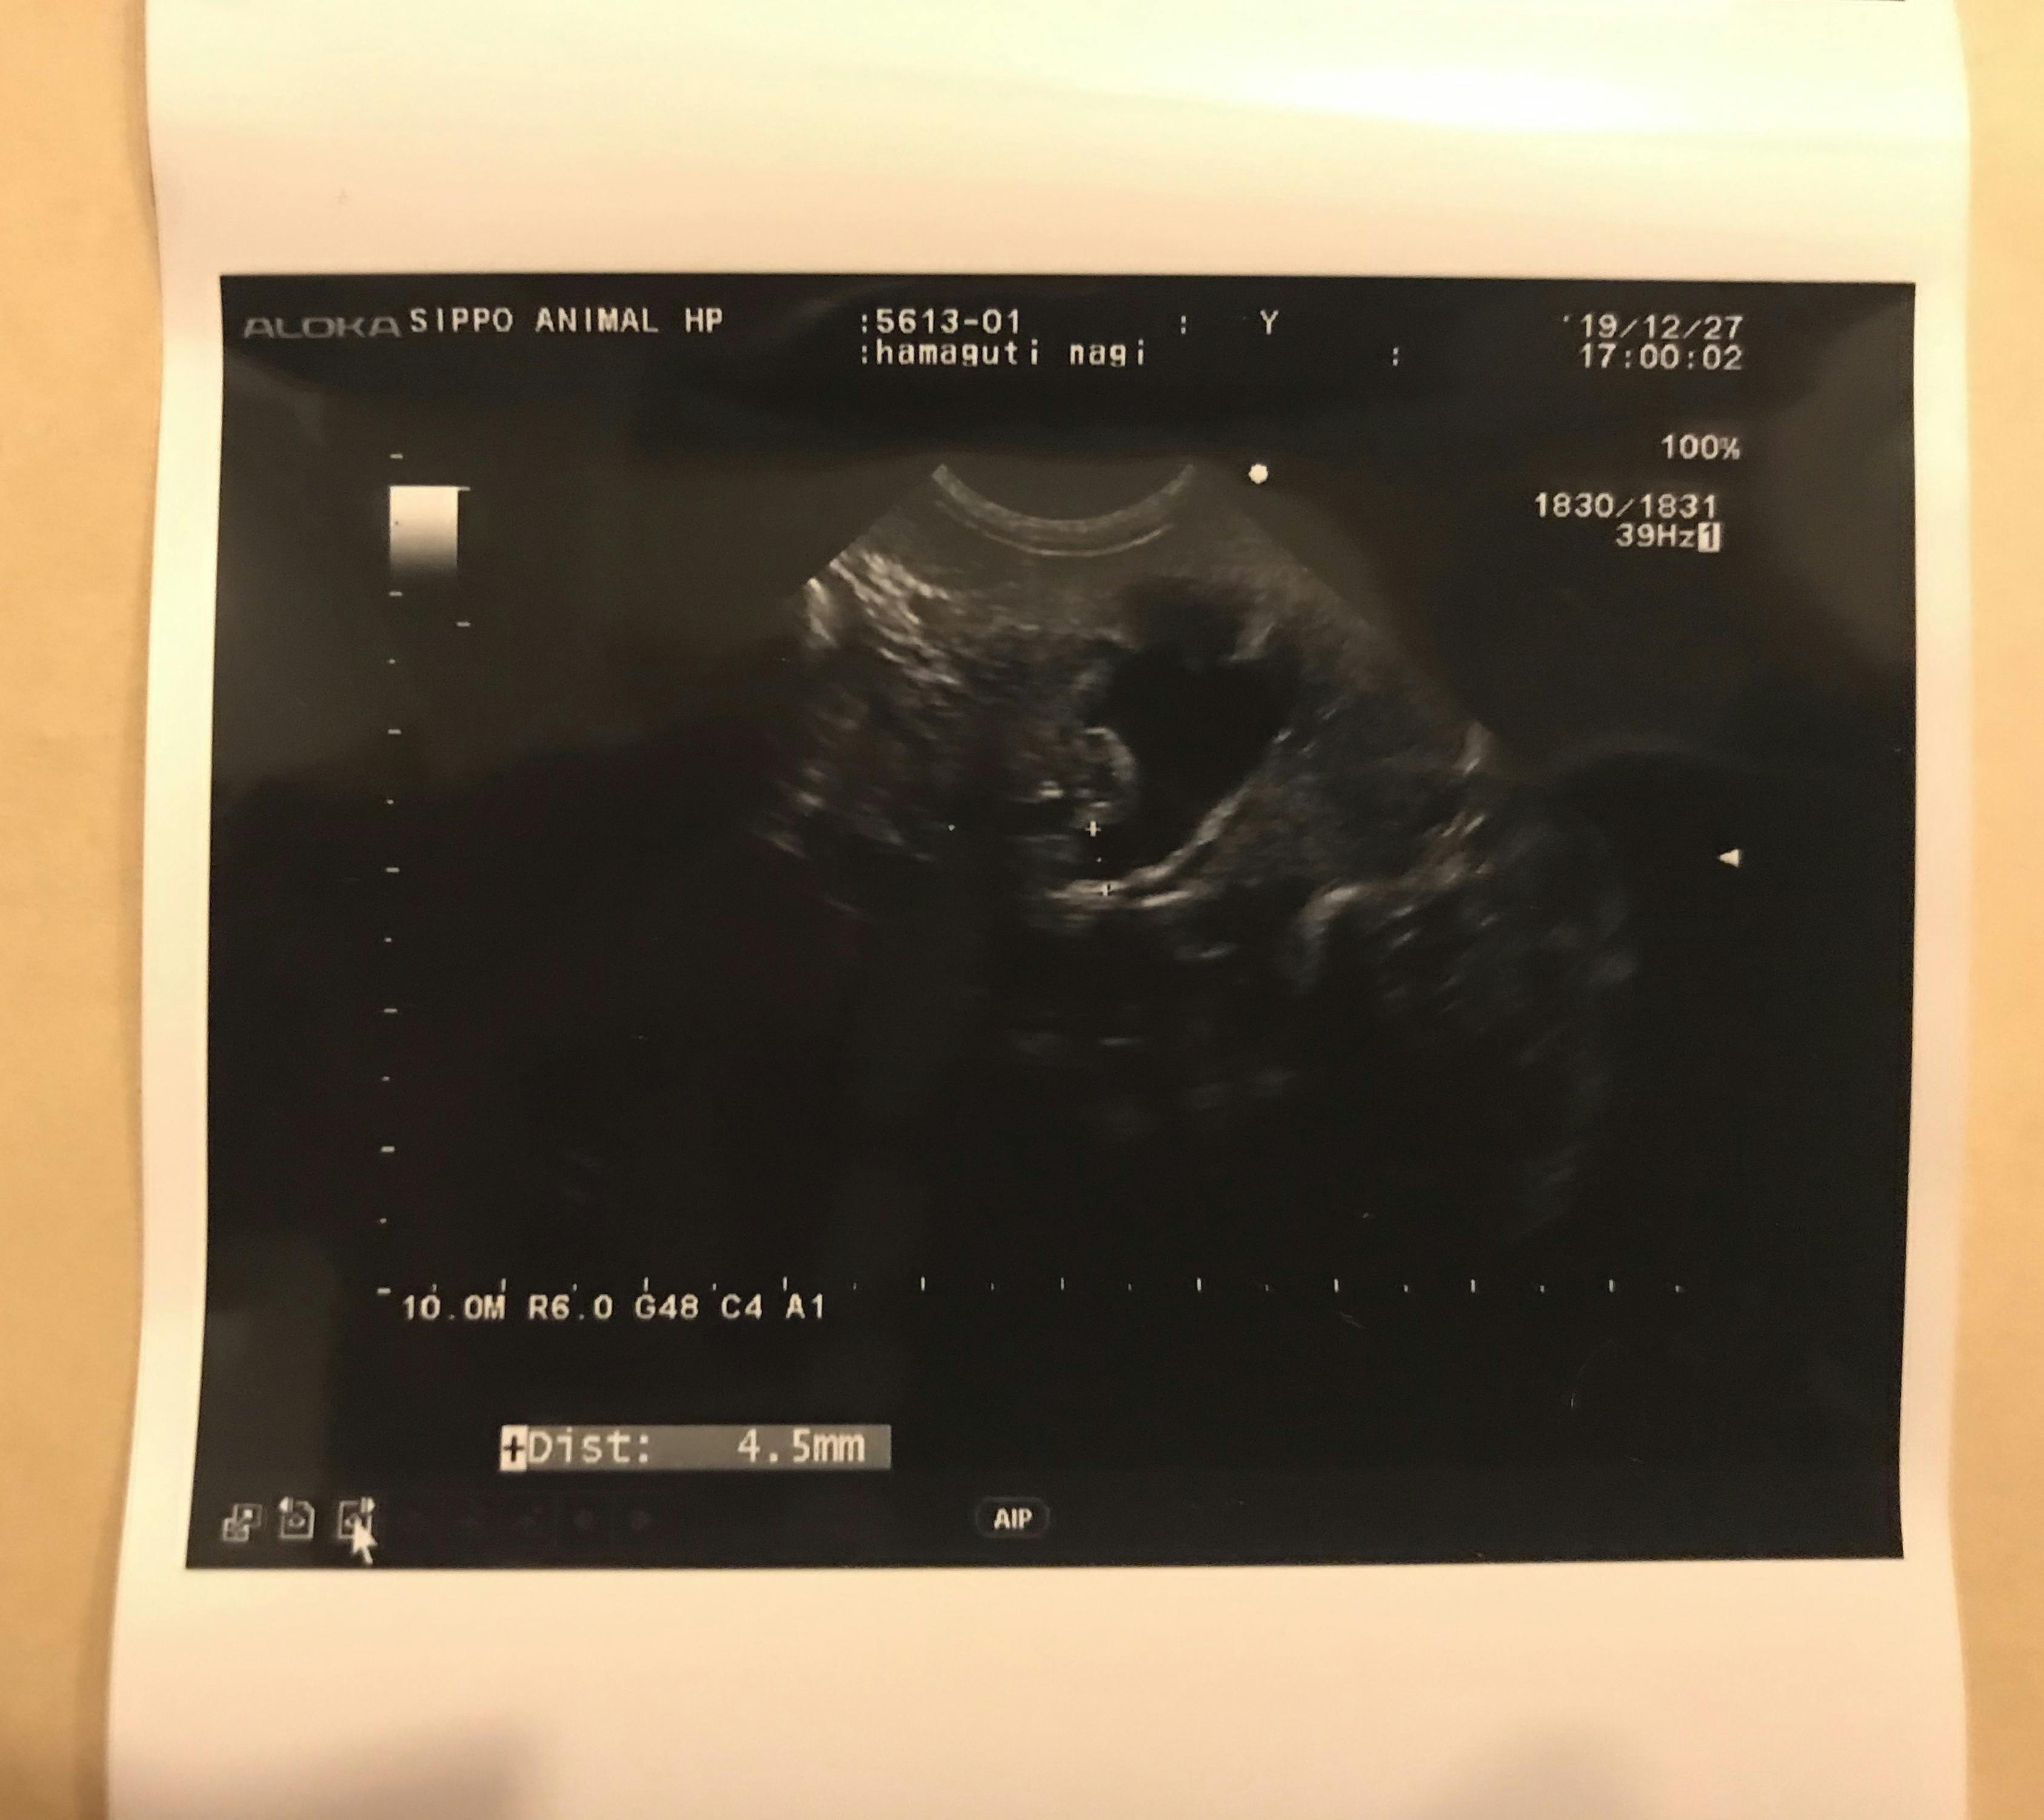

↓腎臓に尿がたまる水腎症も出ていると

エコーの写真で言われました。